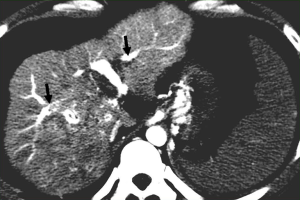

Early enhancement of the portal vein

This is a direct demonstration of a HAPS, usually due to a high-flow arterial fistula, generally a macroscopic arterioportal fistula, transvasal or transtumoral shunt. Two practical findings make this observation easier to diagnose: (I) early main portal vein enhancement, occurring before either the splenic (SV) or superior mesenteric vein (SMV); or (II) early enhancement of peripheral portal vein branches before the common portal vein (Figure 2). Frequently early enhancement will also demonstrate early venous opacification, which can be temporally close to the timing and intensity of the abdominal aorta in the setting of a large shunt.